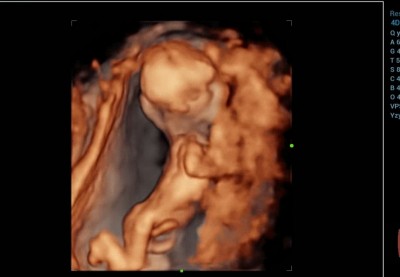

Kızlar detaylı ultrason merkezinde bir radyoloji uzmanı tarafından muayene edildim. İlk önce %99 kız daha sonra %99 erkek dedi. Bacak arasında kordon vardı.  Kafam allak bullak doktor kontrolüne bir hafta var.. Tahmin yürütebilen var mı acaba ya ?

Gebelik haftası 13+6